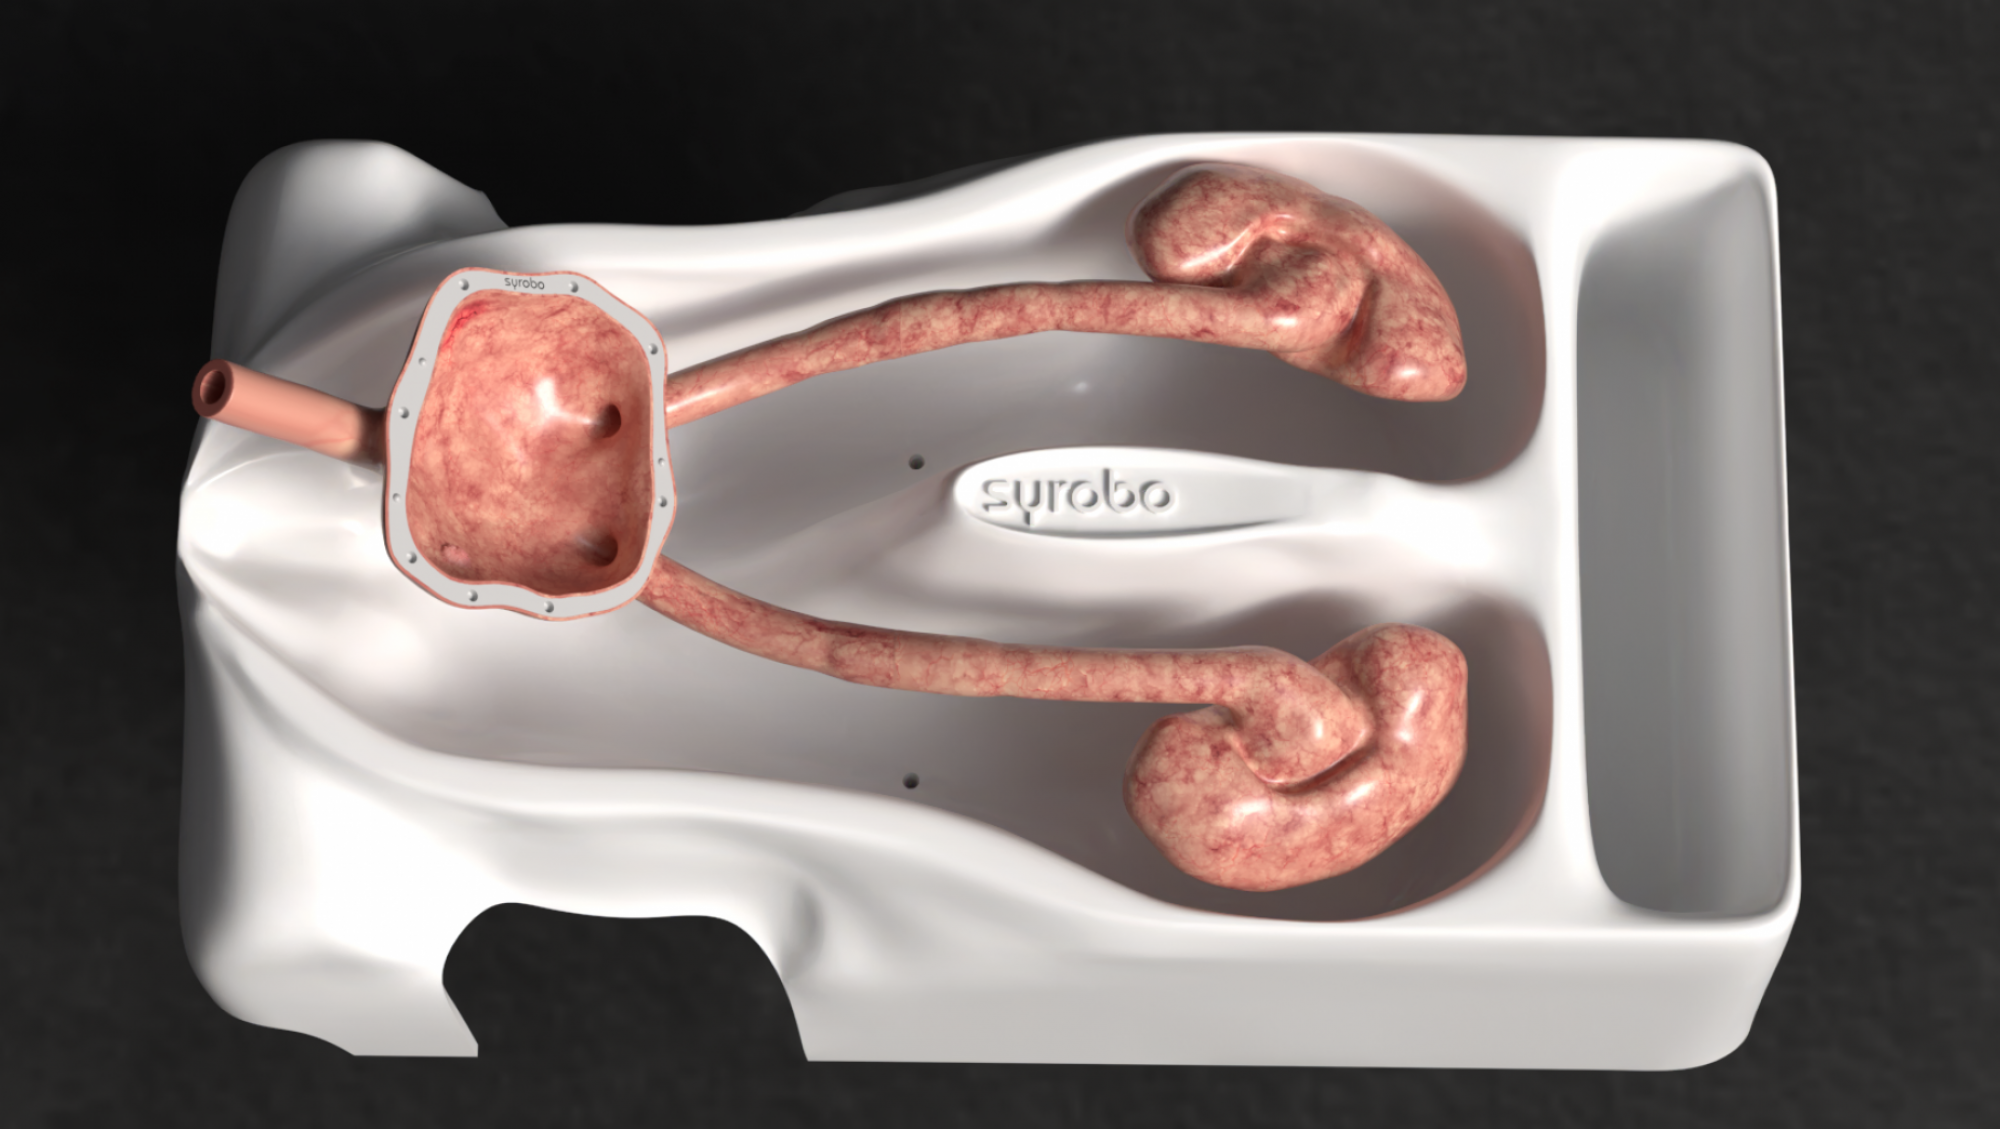

symu is an endo-urology simulator. It’s designed for ease of transport and use, and is housed in a cabin-sized wheeled case. The textured, resin-printed model is renowned for its strength and durability.

The urinary tract components are removable, and feature covers to facilitate the positioning of removable kidney stones or tumors. The model is supplied with dummy stones and removable magnetized tumors.